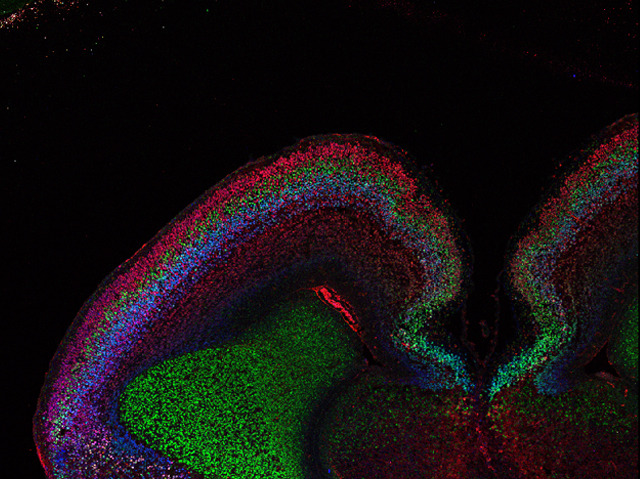

Brain Blot

With as many as 10,000 specific types of neuron in the human brain, unpicking the complex orchestration of development remains a significant scientific challenge. Mouse models have revealed much about how the mammalian brain forms. Sliced vertically this fine film of tissue – from a developing mouse brain – has been stained to show various developing layers, identified by means of different genetic markers. Markers can provide different kinds of information about cells and organisms. A transcription factor [protein that helps switch on genes] called Ctip2 is here stained green. Ctip2 drives the formation of medium spiny neurons in the striatum. These neurons – key to motor ability – are damaged in Huntington’s disease. As scientists identify the processes underlying disease pathology, they pave the way for molecules with therapeutic promise to be tested. In this way, laboratory experiments feed into clinical practice offering the possibility of new treatments for neurodegenerative disease.